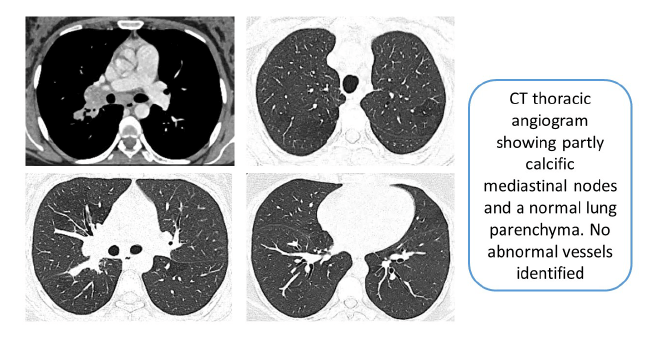

सीटी थोरैसिक एंजियोग्राफी में असामान्य वाहिकाओं का पता नहीं चला, जबकि फेफड़े के पैरेन्काइमा सामान्य दिखाई दिए, हालांकि कुछ मीडियास्टीनल नोड्स के साथ। पिछली ब्रोंकोस्कोपी ने सामान्य निष्कर्षों की सूचना दी थी। हालाँकि, हमारे केंद्र में प्रस्तुत करने पर, दोबारा ब्रोंकोस्कोपी से पूरे ब्रोन्कियल वृक्ष में लाल धब्बे दिखाई दिए, जिससे संदेह पैदा हुआ।